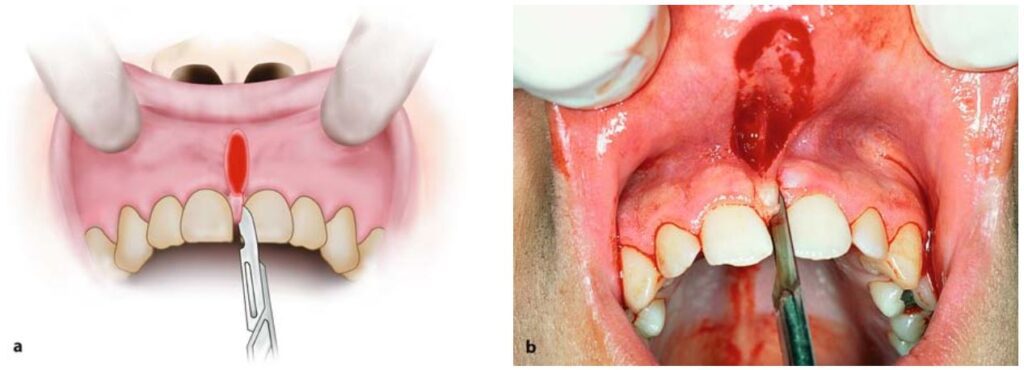

Sau đó kéo căng môi ra hơn nữa rồi dùng dao rạch về phía sau 2 kẹp cầm máu.

Trước tiên rạch phía sau cây kẹp phía dưới, rồi tiếp đến rạch phía sau cây kẹp phía trên (H10.76 – 10.78).